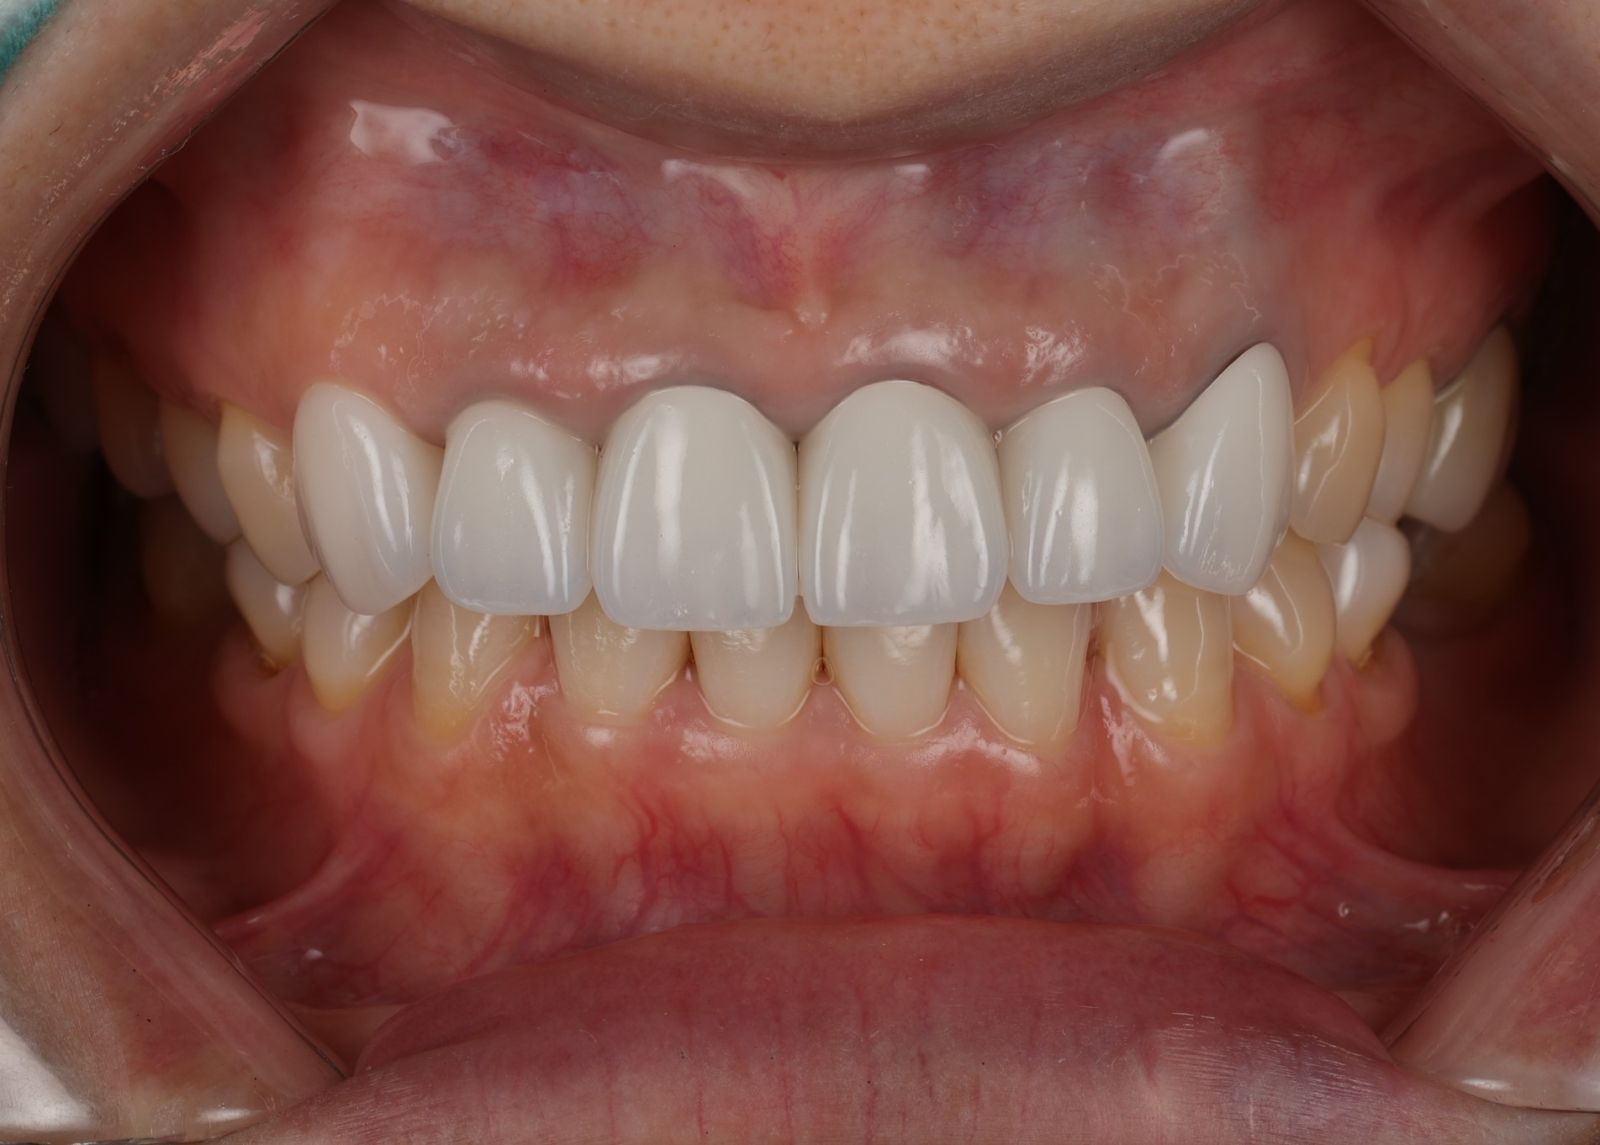

前牙美學是指針對美觀區(通常是門牙、側門牙和犬齒)進行的美容性牙科治療,用意在改善牙齒的外觀,讓笑容更美觀自然。 這包括調整牙齒的顏色、形狀、排列和牙齦的比例,以達到更協調和吸引人的微笑效果。 比較常見的做法有全瓷冠跟美白貼片,需要的話經醫生評估會搭配牙齦整形術。

【 案 例 一 】

- 患者因為以前矯正疏於清潔,很多的蛀牙以及抽過神經的牙齒斷裂缺損,脆弱的牙齒影響健康及美觀。把牙齒磨小的過程會挖除蛀牙,保留健康的牙齒,用陶瓷纖維牙釘維持強度,過程會先用臨時牙套與醫師討論型態,最後依照自己喜歡的顏色及外型設計專屬於自己的前牙美學全瓷冠假牙!